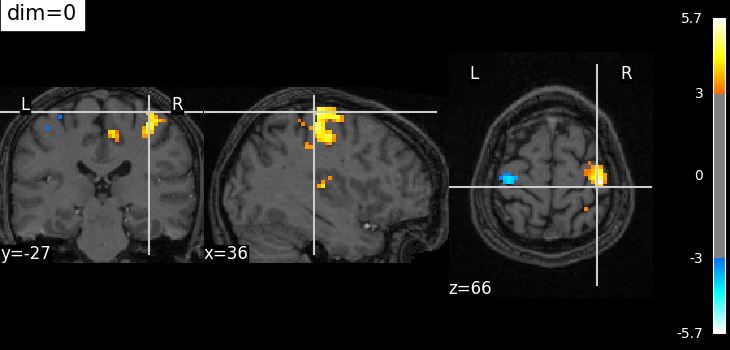

The dim argument controls the contrast of the background.

dim modifies the contrast of this image: dim=0 leaves the image unchanged, negative values of dim enhance it, and positive values decrease it (dim the background).

Plotting with no change of contrast in background image with dim=0¶

plotting.plot_stat_map(

localizer_tmap_filename,

bg_img=localizer_anat_filename,

cut_coords=(36, -27, 66),

threshold=3,

title="dim=0",

dim=0,

)

<nilearn.plotting.displays._slicers.OrthoSlicer object at 0x7f3bd0e9dc10>